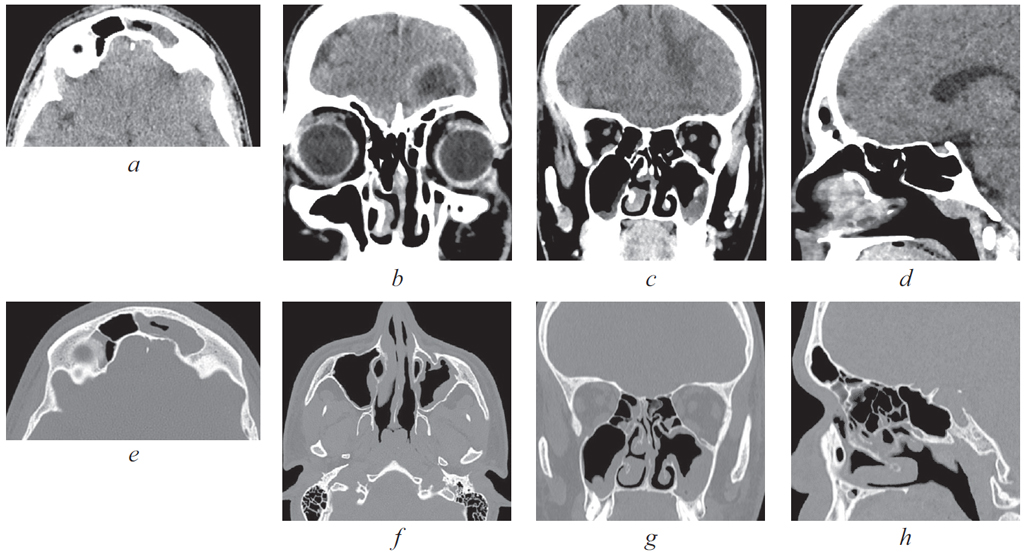

04.06.2021 выполнена мультиспиральная компьютерная томография (МСКТ) ОНП (рис. 1): определяется субтотальное снижение пневматизации левой половины лобной пазухи, задняя ее стенка сохранена, нельзя исключить щелевидные истончения. Затенение лобно-носового кармана слева, клетки решетчатого лабиринта слева частично затенены, деструкции в области переднего основания черепа убедительно не прослеживается. Отмечается пристеночное снижение пневматизации с уровнем жидкости в левой верхнечелюстной пазухе. Округлое новообразование в правой верхнечелюстной пазухе — киста. Пневматизация пазухи клиновидной кости, клеток сосцевидных отростков и барабанных полостей не нарушена.

Рис. 1. Мультиспиральная компьютерная томография околоносовых пазух и головного мозга от 04.06.2021: коронарная (а) и аксиальная (b) проекции в режиме skull, субтотальное затенение левой лобной пазухи, костная деструкция отсутствует; аксиальная (c) и сагиттальная (d) проекции в режиме brain, эпидуральная эмпиема левой лобной области головного мозга; коронарная (е) и аксиальная (f) проекции в режиме brain с контрастным усилением. Эпидуральная эмпиема левой лобной области головного мозга. Отчетливо прослеживается капсула

Fig. 1. Multispiral computed tomography of the paranasal sinuses and brain from 04.06.2021: coronal (а) and axial (b) projections in the protocol of the skull, subtotal shading of the left frontal sinus, no bone destruction; axial (c) and sagittal (d) projections in the brain mode, epidural empyema of the left frontal area of the brain; coronary (е) and axial (f) projections in brain mode with contrast enhancement. Epidural empyema of the left frontal region of the brain. The capsule is clearly visible

04.06.2021 выполнено МСКТ головного мозга: определяется наличие очага гнойного воспаления, исходящего из левой лобной пазухи и отграниченного от вещества мозга капсулой. Наличие двух очагов малого размера («отсевы»), менее 1 см, с признаками формирующейся капсулы. Отмечается зона отека мозгового вещества между очагами.